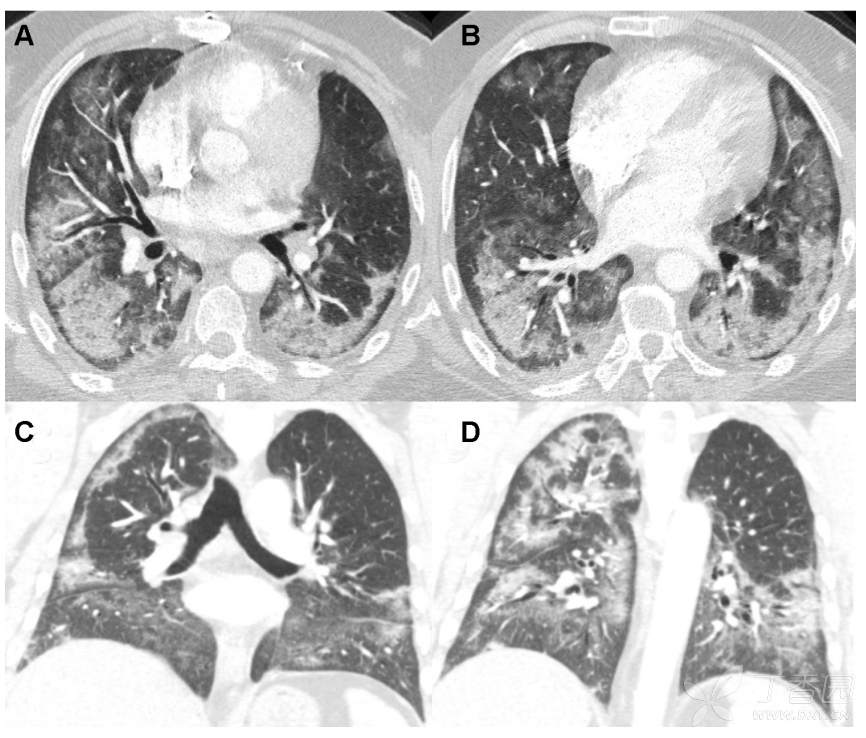

57岁男子干咳气短1月,病理已经做,诊断?

男性 57 岁因干咳和气短一月就诊 。

患者2 个月前经历了一次干咳和气短。临床诊断他患有上呼吸道疾病 感染,仅保守治疗7天后症状消失。一个月后,干咳和气短又发,接受了为期5天的治疗口服阿奇霉素疗程后症状没有任何改善。

因怀疑间质性肺疾病,予电视胸腔镜下肺活检,病理如下:

What is the diagnosis?

请诊断!